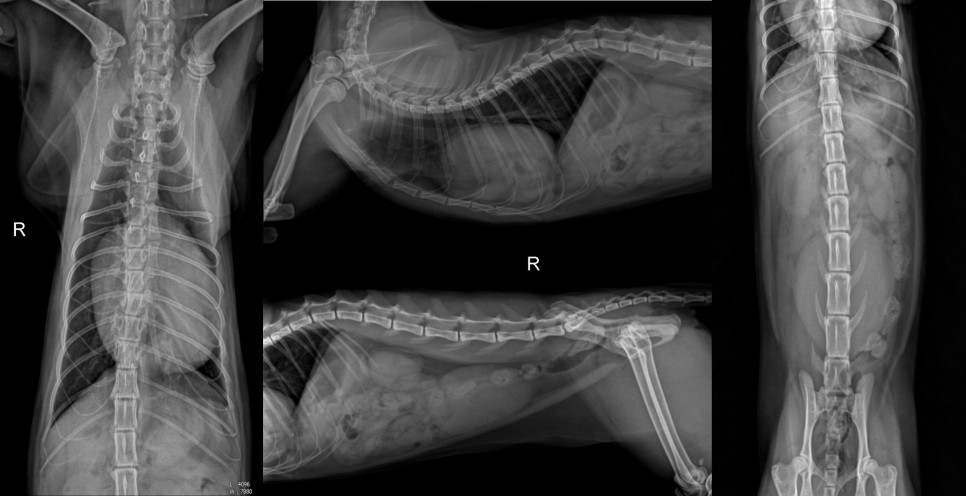

주요 증상으로 내원하기 전날부터 급격한 식욕저하와 반복적인 구토 증세로 타원하여 횡격막 탈장이 의심된다는 소식을 듣고 정밀검사와 수술을 위해 본원에 내원하였습니다. X-ray

X선 검사에서 정상적으로는 복강 내에 있어야 하는 위와 소장분절, 간의 일부가 심낭 안으로 변위되어 있는 것이 확인되었으며, 횡격막탈장 중 복막심낭 횡격막탈장(PPDH)으로 판단되었습니다.